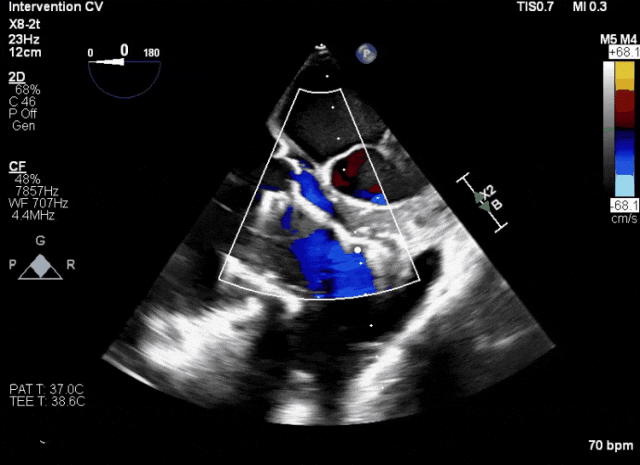

術(shù)前超聲顯示三尖瓣重度反流合并拴系